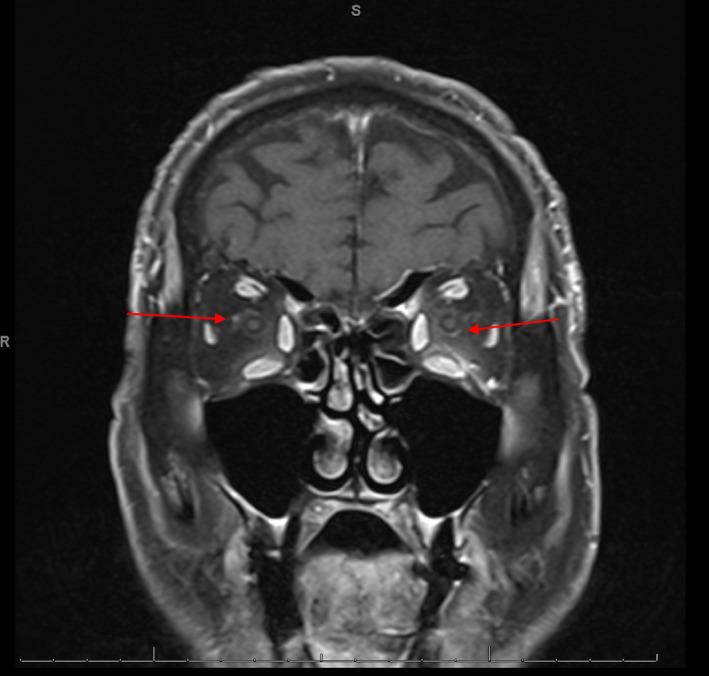

We report a fatal case of myasthenia gravis, myositis, and cardiotoxicity overlap syndrome precipitated by the ICI pembrolizumab along with a brief review of available literature.

我们报告了一例由 ICI 派姆单抗诱发的重症肌无力、肌炎和心肌毒性重叠综合征致死病例,并对现有文献进行了简要回顾。